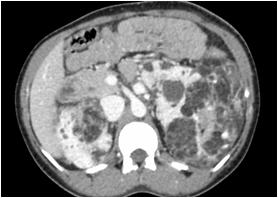

Radiological imaging was done in all the cases. USG findings revealed solitary masses in 45 cases (80.35%) and diffuse masses in 11 (19.64%). Solitary masses were around 45 in number out of which 30 were diagnosed as HCC. Right lobe had around 30 (66.7%) whereas left lobe had 15 (33.33%) masses respectively. Maximum (SOL’s) observed showed hyper-echogenicity present in 43 cases (76.78%). Heterogenous echotexture was observed in 6 cases (10.71%) (Fig 1).

CT scan was done in two patients which showed multiple well defined hyperdense lesions and hypodense lesions in another patient. Cyto-radiological correlation of hepatic masses was seen in 94% cases (Fig 2).

Fig 1 — USG liver showing well defined heteroechoic lesion in left lobe

Fig 2 — CT liver showing multiple enhancing focal hepatic lesions suggestive of metastasis